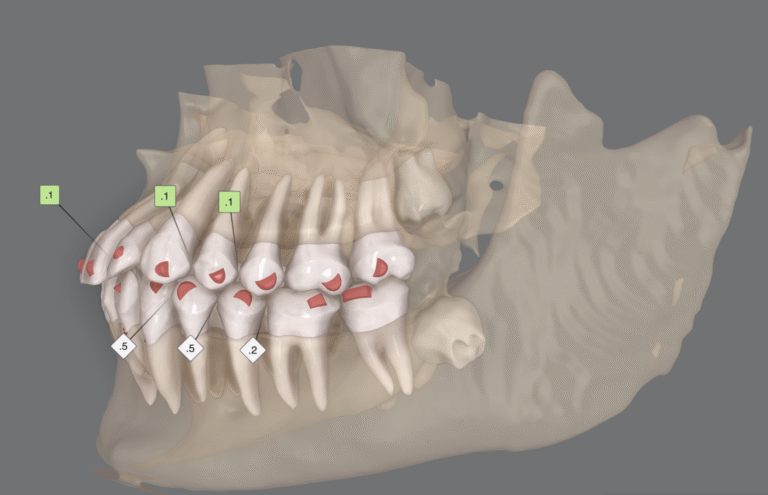

Empezemos por lo que ya sabíamos: una intrusión pura de 2mm es relativamente sencilla de conseguir con alineadores, siempre que la secuencia sea buena y el sistema de anclaje en ataches resulte eficiente.

Por eso nosotros en sistema de biomecánica avanzada nos enfocamos en la posición final del incisivos respecto de sus bases óseas y, si bien intentamos minimizar siempre los movimientos de vaivén, asumimos que pueden ser necesarios para conseguir valores de intrusión mayores de 2mm.

Además de esto, planificar la intrusión con espacios interdentales de 0,1 o 0,2mm reduce la fricción entre las piezas y mejora los resultados de manera sencilla, sobre todo en casos en los que hemos planificado stripping, el cual no siempre realizamos con una precisión del 100%.